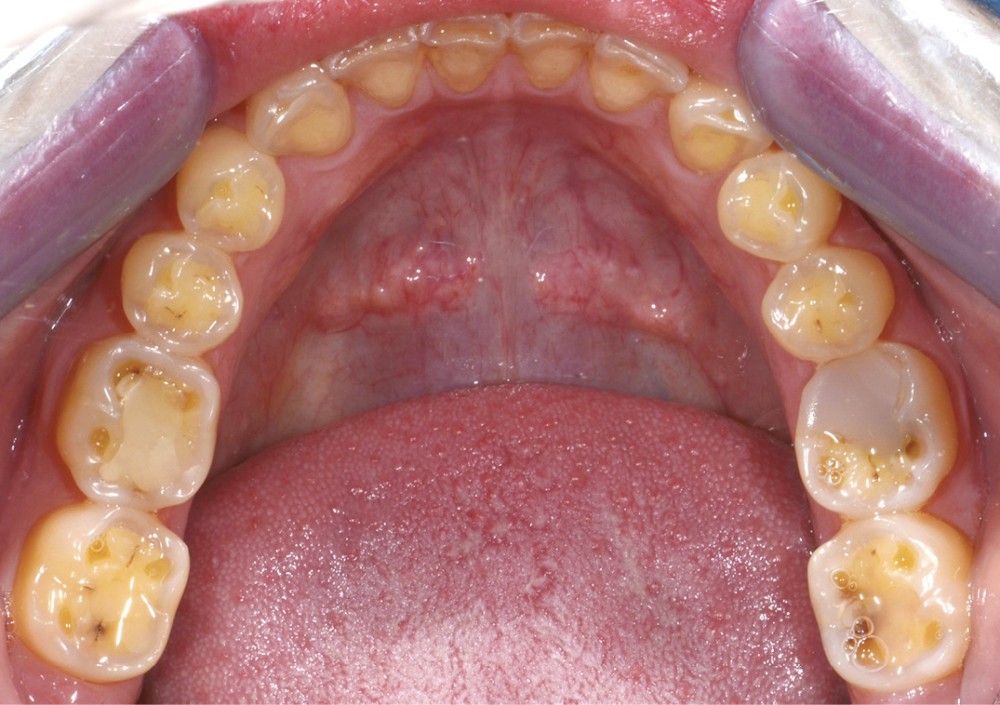

Une patiente âgée de 28 ans se présente en consultation avec une inquiétude au sujet de ses dents postérieures : elle a observé une usure avec un « jaunissement » des faces occlusales et se plaint de sensibilités répétées (fig. 1 à 3).

L’examen général met en évidence un bruxisme nocturne ainsi qu’une consommation peut-être excessive d’agrumes.